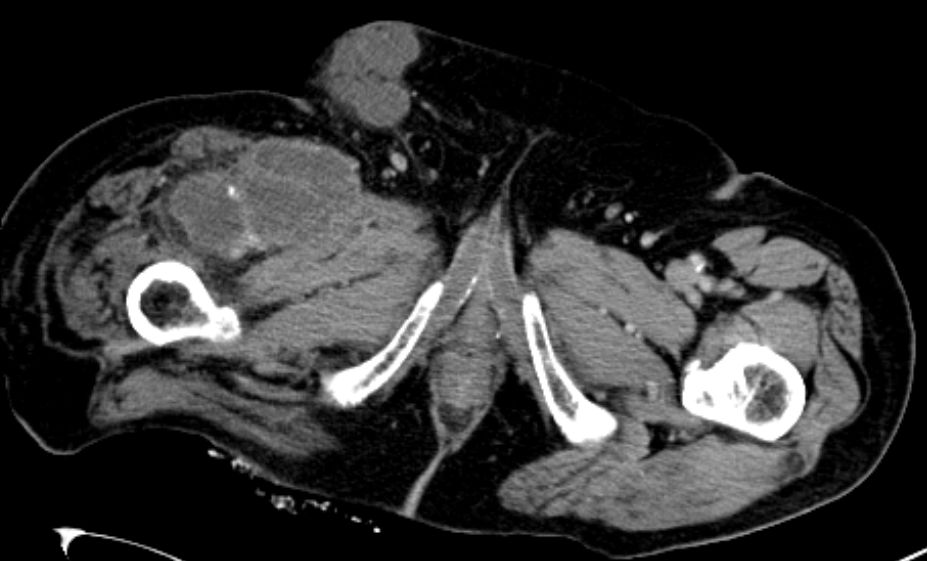

74-jähriger Mann, der vor 2 Jahren eine Beinamputation rechts wegen eines Chondrosarkoms der Tibia hatte. Jetzt ausgedehnte Knoten in der rechten Leiste. |